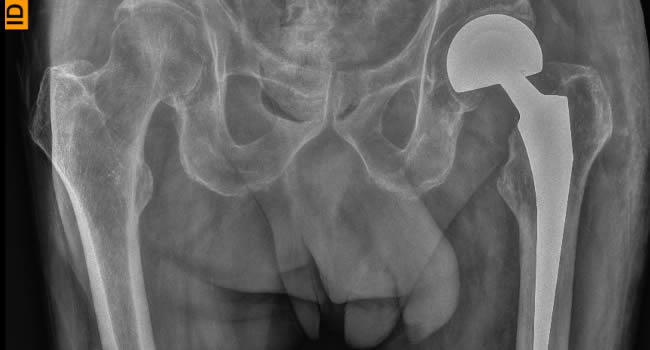

Οι ακτινογραφίες πραγματοποιούνται με πλήρως ψηφιακό εξοπλισμό και όχι ψηφιοποιημενο από έμπειρους Τεχνολόγους – Ακτινολόγους με άδεια ασκήσεως Επαγγέλματος.

Ο πιο σύγχρονος φορητός Ακτινολογικός εξοπλισμός πλήρως ψηφιακής απεικόνισης (DR) σε μια κινητή ακτινολογική μονάδα, μπορεί να επισκεφθεί τον ασθενή οπουδήποτε στην περιοχή της Θεσσαλονίκης και των περιχώρων και να σταλεί, αν ο ασθενής το επιθυμεί, η γνωματευμένη ακτινογραφία ηλεκτρονικά μέσω διαδικτύου στον θεράποντα- παραπέμποντα ιατρό ο οποίος θα λάβει το αποτέλεσμα στο προσωπικό του υπολογιστή, tablet, Smartphone οπουδήποτε κι αν βρίσκεται.